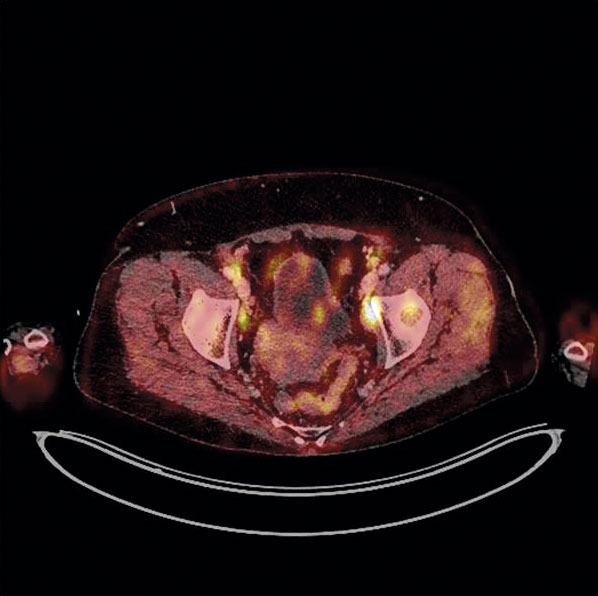

PET-DT med FDG. Vid PET-DT med FDG används den positronemitterande isotopen 18-fluorodeoxiglukos. Isotopen är en radioaktiv glukosanalog med en halveringstid på 110 min och tas upp av vävnad med hög glukosmetabolism, som tumörvävnad. Metoden kan inte säkert skilja mellan inflammation och malignitet utan speglar grad av glukosmetabolism i förändringen. Fynd med högt FDG-upptag (PET-positiva) ska därför verifieras cytologiskt eller histopatologiskt [22]. Bilden visar fokala patologiska höga FDG-upptag i iliakala lymfkörtlar med stark malignitetsmisstanke.